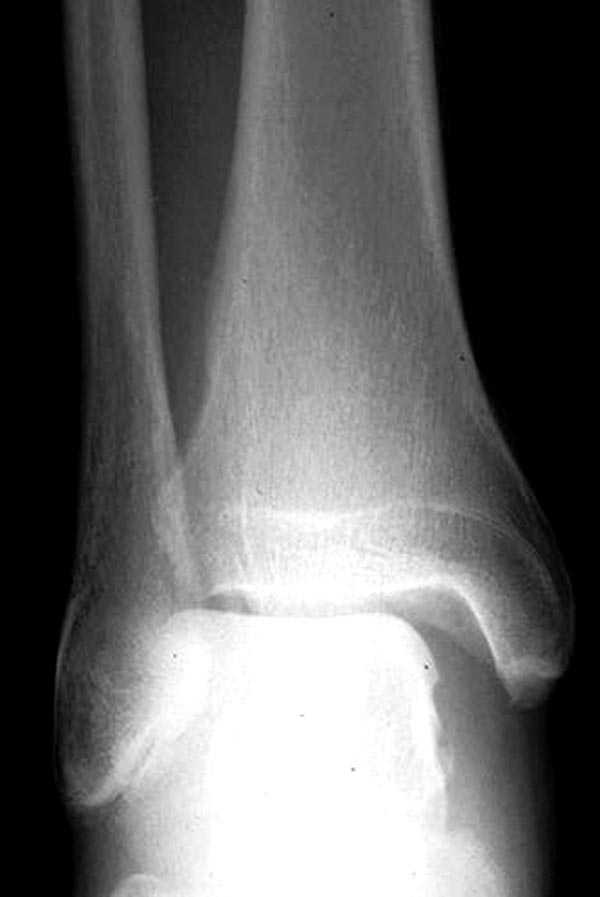

>отмечает боли в правом голеностопном суставе,патологической подвижности правой стопы нет

Может имеет смысл сделать снимки с центрацией на голеностопный сустав и стрессовые рентгенограммы его же? Если механизм травмы непрямой. то возможны сопутствующие повреждения г/с

Перелом малоберцовой кости есть, понятно. Но боли в голеностопном суставе! А как вы изучали патологическую подвижность стопы? Есть стрессовые снимки?

Вопрос, который возникает у меня при виде таких снимков,- "Какой механизм травмы?"

Если это прямой удар, то кроме перелома м,б кости и ушиба мягких тканей ничего нет.

Если механизм непрямой, т.е. подворачивание (ротация) стопы, то это повреждение надо классифицировать как нестабильный перелом лодыжек (44 С.2) с повреждением синдесмозных связок.... Да, на обычных рентгенограммах можно

видеть идеальный голеностопный сустав

здесь пропускаем повреждение Maisonneuve...

Здесь как раз тот случай, когда рентгеновский снимок скрывает главную проблему. "Ходит, прихрамывая на правую ногу, отмечает боли в правом голеностопном суставе" По описанию клиника типичная для повреждения голонестопного сустава - синдесмоза.

При проксимальных переломах малоберцовой автоматически необходимо подозревать повреждение синдесмоза - Maisonneuve Fracture.

"На западе", как правило, при переломах голеностопа требуются снимки проксимальной части голени.

Описанное в 1840 году Maisonneuve повреждение характеризуется тем, что при фиксированной наружной ротации стопы повреждается передняя фибуло-тибиальная связка, часть синдесмоза, с переломом медиальной лодыжки и без, дальше разрыв продолжается по межкостной мембране и спиральный или косой перелом малоберцовой происходит выше.

Для уточнения диагноза надо сделать все стандартные снимки голеностопа, (несмотря на необходимость при любых повреждениях голеностопа, почему-то очень трудно воспроизводится коллегами из СНГ?)

На прямой проекции можно увидеть расширенную медиальную щель, и на мортизе укорочение малоберцовой.